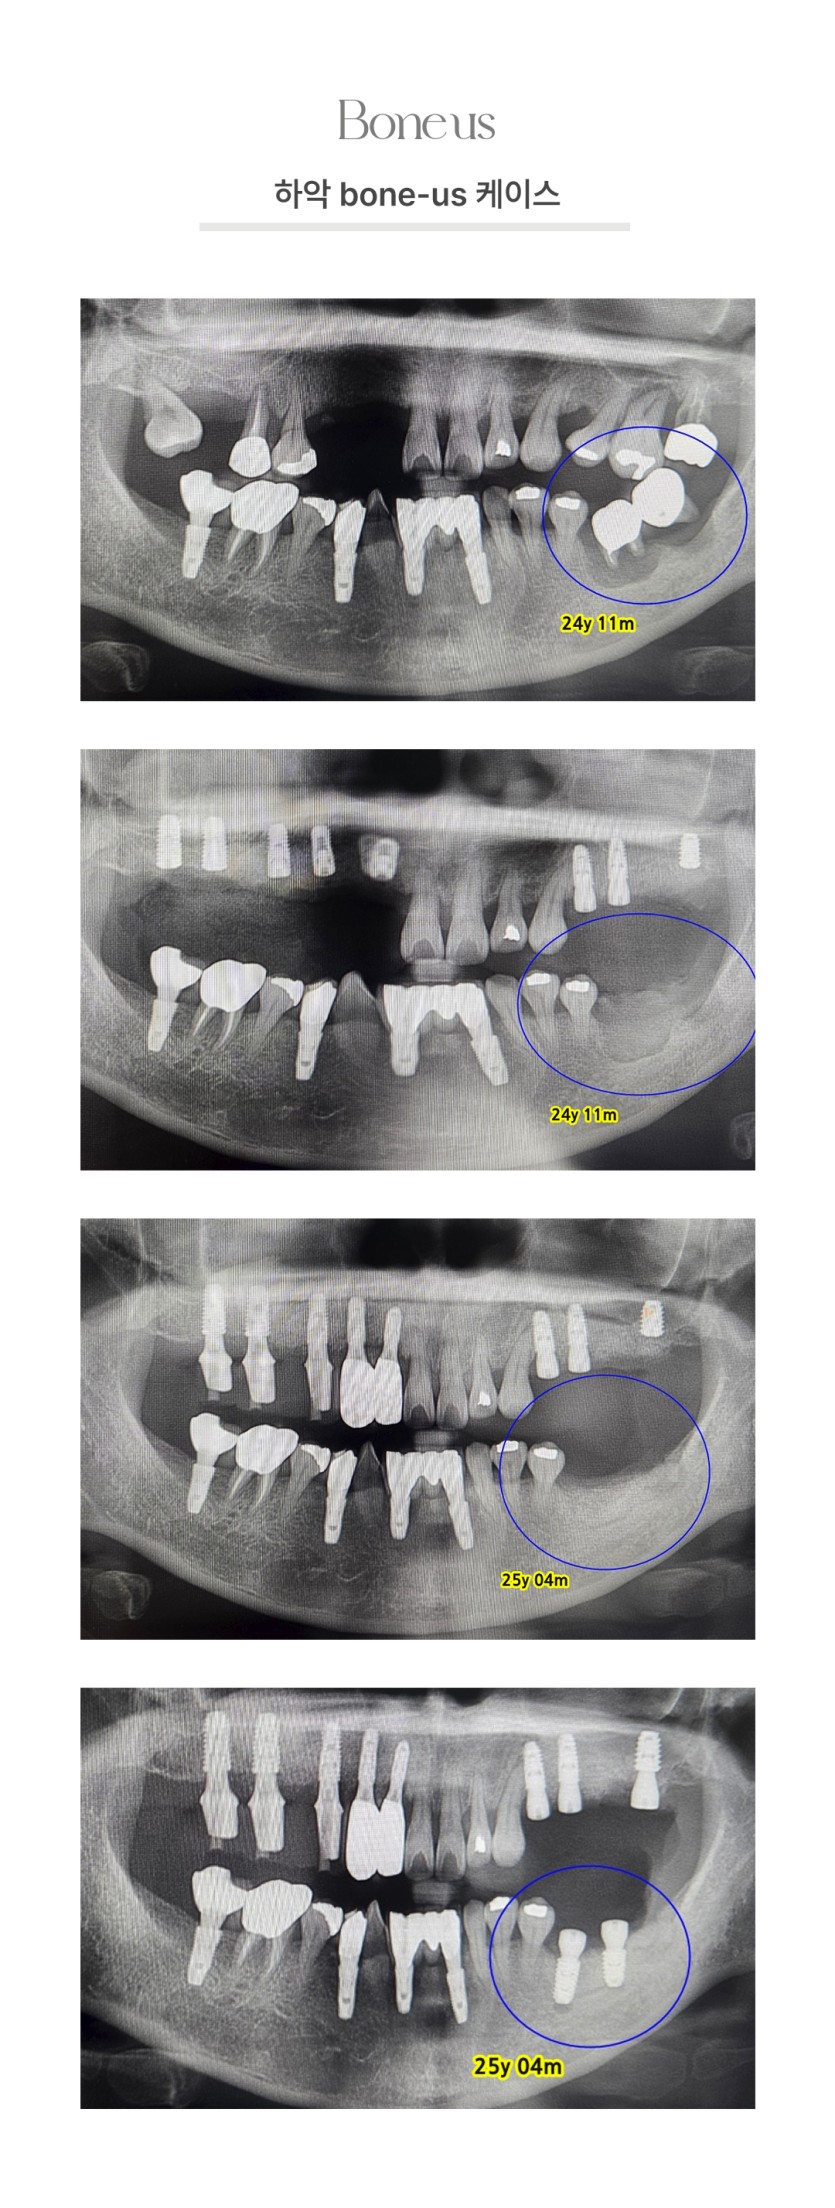

본어스 시술사례

하악 본어스 케이스 1

하악 본어스 케이스 2